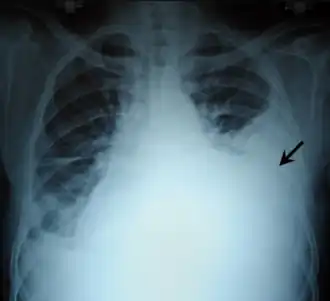

Hemothorax, aangegeven met pijl

Een hemothorax is een abnormale toestand waarbij er bloed in de pleurale ruimte gelekt is, met als gevolg dat de long kleiner geworden is. Deze toestand wordt meestal veroorzaakt door een trauma waardoor een bloeding ontstaan is. De hoeveelheid bloed kan eventueel toenemen tot een situatie waarbij er zoveel druk op de longen uitgeoefend wordt dat de werking hiervan gehinderd wordt, of tot er zoveel bloed aan de circulatie is onttrokken dat de patiƫnt in shock raakt.